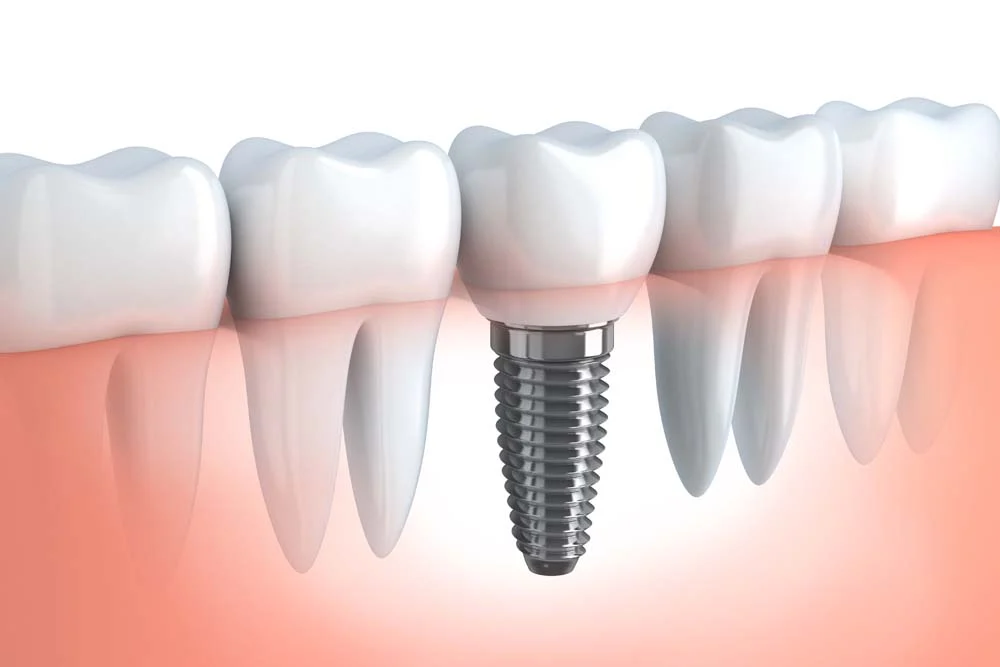

Un impianto dentale è una delle soluzioni più moderne e durature per sostituire un dente mancante. Questo dispositivo è realizzato in titanio, un materiale biocompatibile che consente all’impianto di integrarsi perfettamente con l’osso mascellare, processo noto come osteointegrazione. Gli impianti dentali sono progettati per supportare una corona dentale, un ponte o una dentiera, ripristinando la funzione masticatoria e migliorando l’estetica del sorriso.

Cos’è un impianto dentale e i suoi componenti principali?

Un impianto dentale si compone principalmente di tre parti:

- Vite: la parte che viene inserita nell’osso mascellare, fungendo da radice artificiale.

- Moncone: una parte che si avvita sulla vite, fungendo da supporto per la corona.

- Corona: la parte visibile dell’impianto, che riproduce l’aspetto del dente naturale.

Ogni componente gioca un ruolo cruciale nel garantire che l’impianto funzioni correttamente. La vite, in particolare, è progettata per stabilizzarsi nell’osso, creando un collegamento solido e sicuro. Questo processo è essenziale per garantire la durata dell’impianto nel tempo.